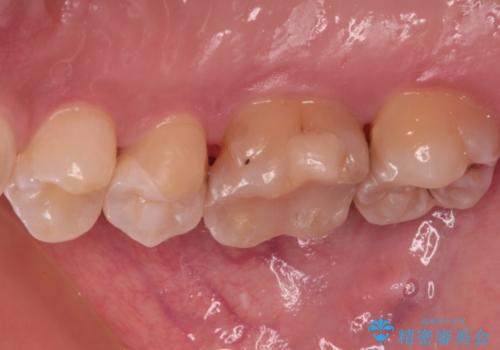

- 以前詰め物をした奥歯に物が頻繁に挟まるとのことで来院された患者様です。

充填物は形態が不正であり、歯肉付近にバリのように充填材料が飛び出していたため、歯肉が腫れやすい状態でした。

精密に治療を行うため、型取りを行った上でセラミックインレーによる修復治療を行うこととしました。